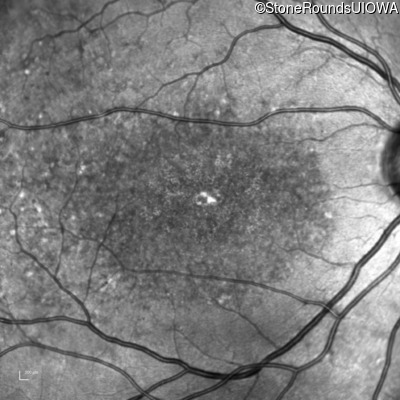

This 16 year old female first had difficulty seeing the blackboard at age 9. Her eye doctor at the time felt at the time that she was "faking it". More recently her eye doctor told her she would be blind by age 20 and suggested she get a seeing eye dog.

| Age at visit: 16 years |